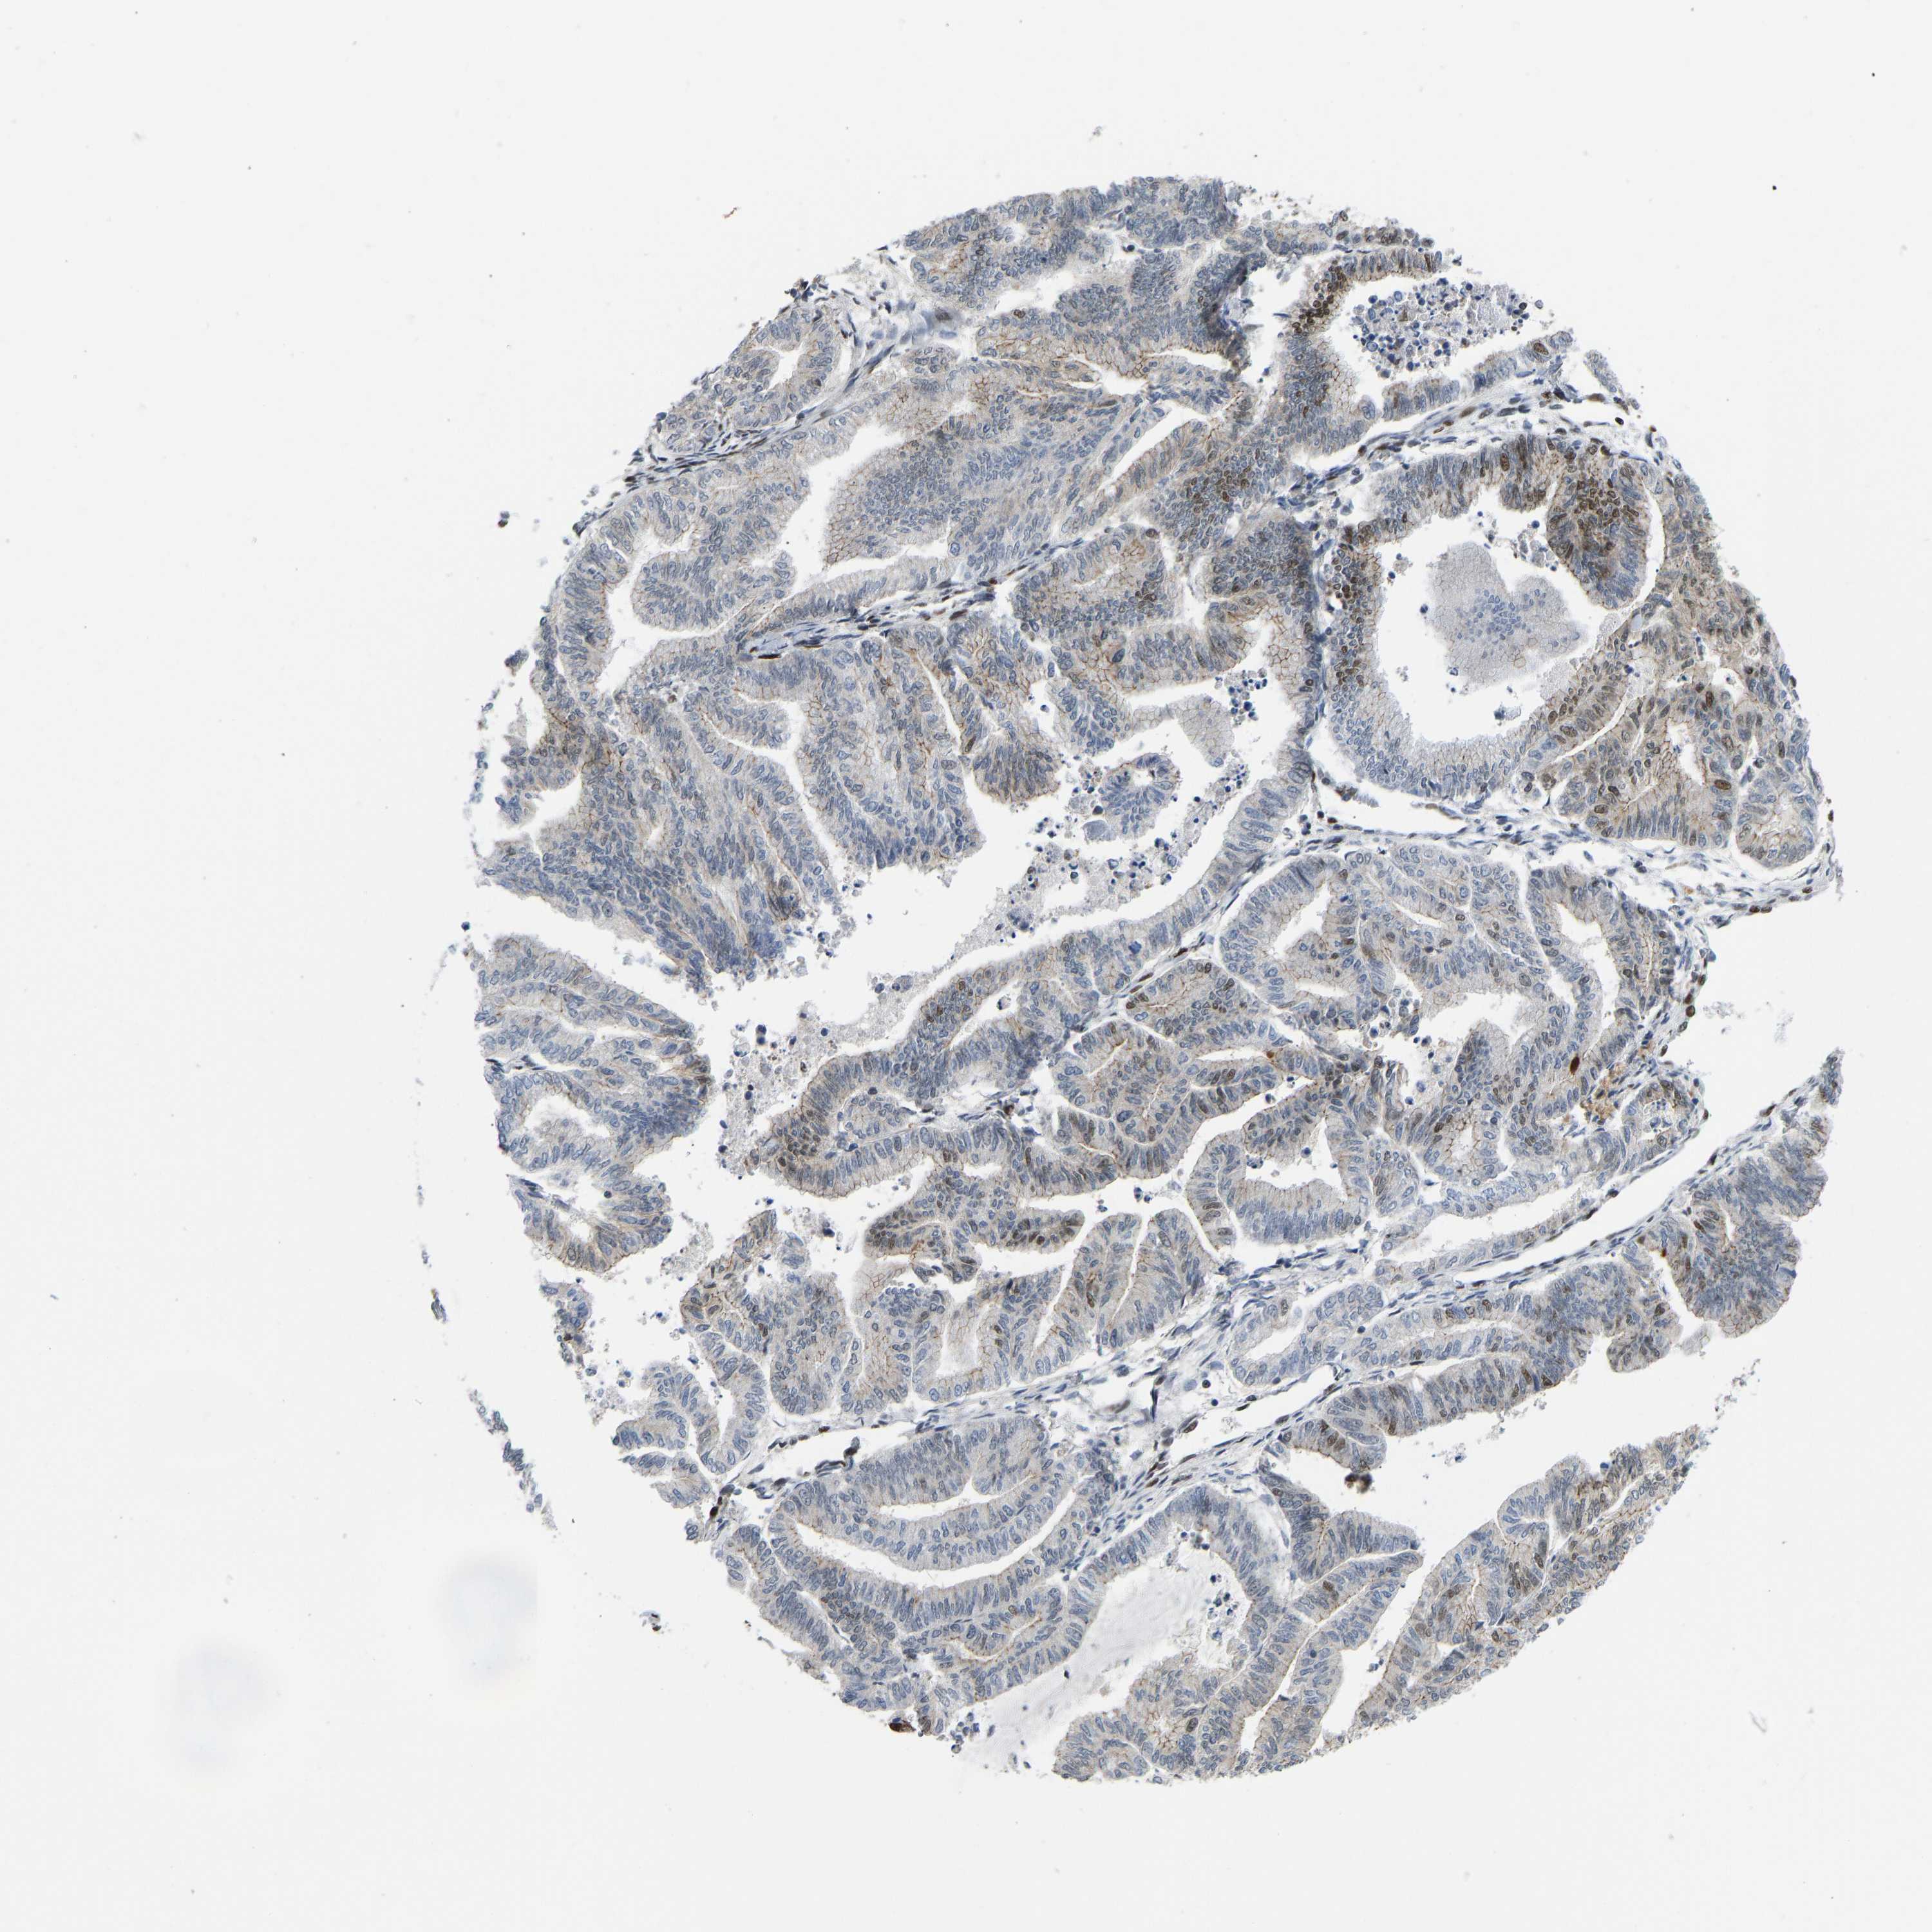

ENDOMETRIAL CANCER - Protein expressioni

A mouse-over function shows sample information and annotation data. Click on an image to view it in a full screen mode. Samples can be filtered based on level of antibody staining by selecting one or several of the following categories: high, medium, low and not detected. The assay and annotation is described here.

Note that samples used for immunohistochemistry by the Human Protein Atlas do not correspond to samples in the TCGA dataset.

Antibody stainingi

Antibody staining in the annotated cell types in the current human tissue is reported as not detected, low, medium, or high, based on conventional immunohistochemistry profiling in selected tissues. This score is based on the combination of the staining intensity and fraction of stained cells.

Each image is clickable and will lead to virtual microscopy that enables deeper exploration of all samples and also displays staining intensity scores, fraction scores and subcellular localization as well as patient and tissue information for each sample.

Antibody HPA017998

Antibody HPA018864

Staining

High

Medium

Low

Not detected

Intensity

Strong

Moderate

Weak

Negative

Quantity

>75%

75%-25%

<25%

None

Location

Nuclear

Cytoplasmic/membranous

Cytoplasmic/membranous,nuclear

Adenocarcinoma, NOS